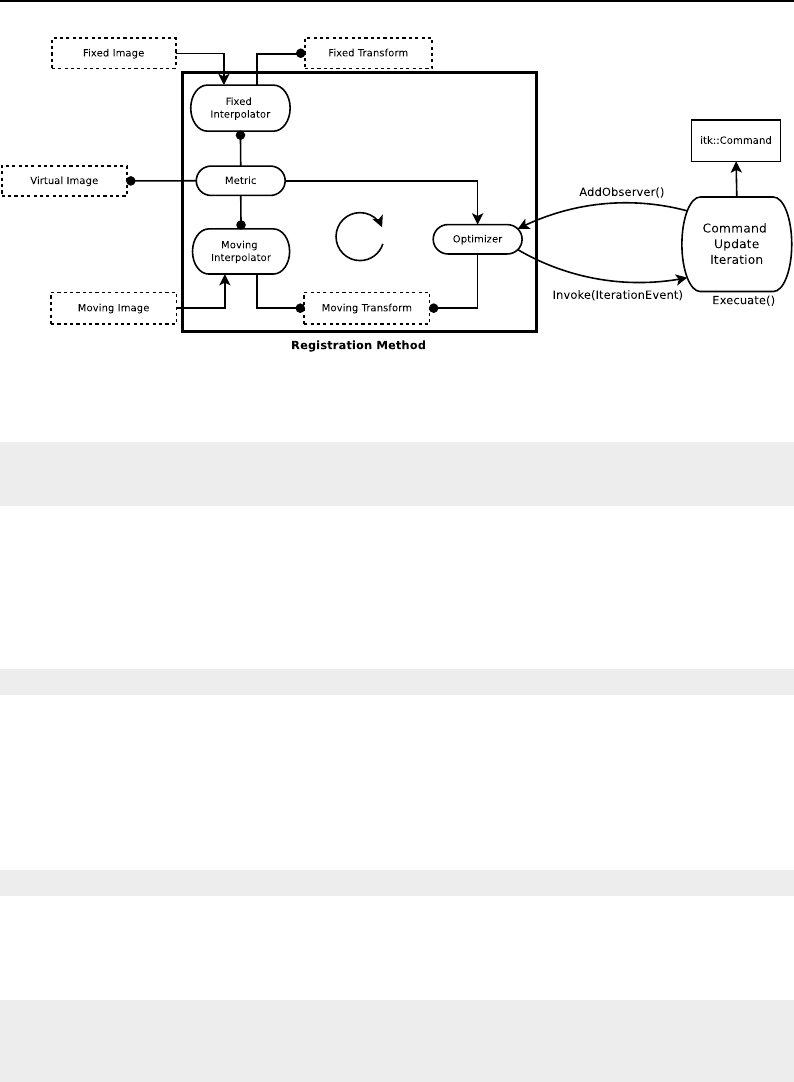

- Registration Framework

- "Hello World" Registration

- Features of the Registration Framework

- Monitoring Registration